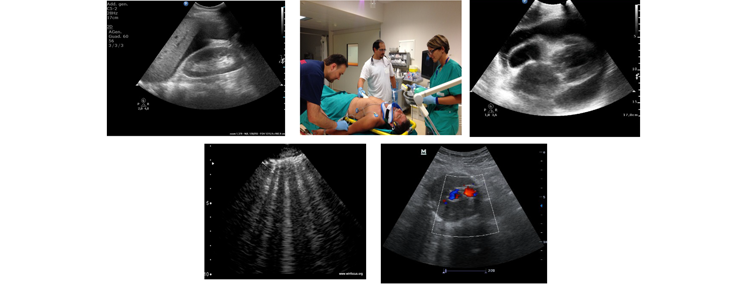

DIAGNOSTICA ECOGRAFICA IN EMERGENZA: CORSO TEORICO-PRATICO

Il Corso è rivolto a Medici di Medicina d’Emergenza, Urgenza e Pronto

Soccorso, Anestesia/Rianimazione, Chirurghi e a tutto il Personale Medico che opera nell’Emergenza intra-Ospedaliera e/o Territoriale. Ha lo scopo di fornire le conoscenze teorico- pratiche necessarie ad utilizzare la metodica dell’ultrasonografia applicata a 360 gradi in situazioni di emergenza ed urgenza medica, chirurgica e traumatologia, di peri-arresto ed arresto cardiaco, tutto ciò in integrazione alle linee guida ALS ed ATLS.